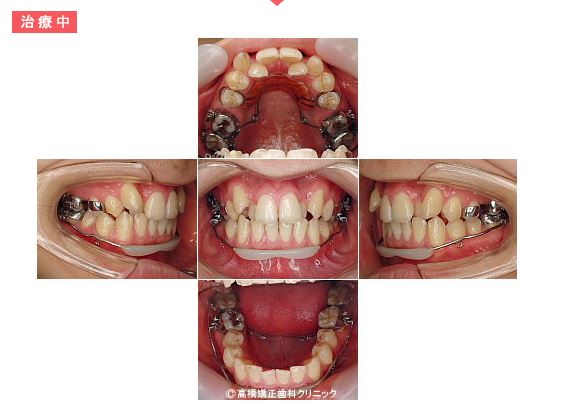

治療中

まず上下の奥歯をゆっくりと後方に移動していきます。